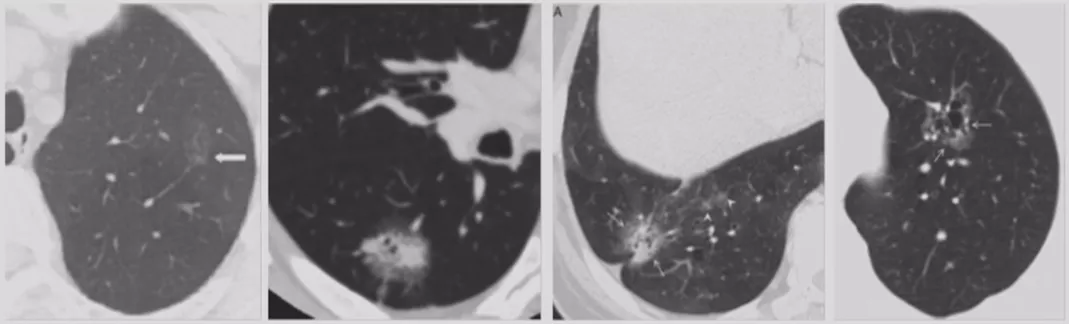

如上图所示,一般来说这么小的病灶我们可能忽略,但这个病人做了手术,不仅是恶性肿瘤,而且是微浸润腺癌。实际上我们在临床上要把这么多结节甄别出来,是十分具有挑战性的。病人一旦患有肺结节,也面临着很多问题,比如焦虑、心理压力等。所以我们既不能过度诊断,但也不能延误诊断。

在临床上经常手术切除后发现是AAH,关于AAH的病人是否需要手术还存在很大的争议,有的认为不需要手术,观察就可以。那么我们在术前怎么评判是否为AAH?其实具有一定特征。一般来说,多位于肺外周,多<5mm,圆形或类圆形,边界清楚,多发更常见,绝大部分是均匀的纯磨玻璃影,里边没有实性成分。组织学检查AAH呈轻度到中度非典型立方柱状上皮细胞沿肺泡和呼吸性细支气管上皮增殖,无浸润,这样在临床上诊断AAH应该没有问题。但是,如下图所示,这个病人是多灶性病变,现在多灶性结节有所增多,会给临床的处理上带来一定压力。

小细胞肺癌以中央型多见,但是也有少数为周围型病灶。多为单个实性结节或肿块,可见分叶、毛刺、血管集束征、胸膜牵拉征。实际上我们很难从影像学上判断出小细胞肺癌的病理类型,往往是活检或者手术以后才能证实。如下图示,这属于I期的小细胞肺癌,进行手术的效果非常好。所以对于周围型小细胞肺癌,如果在结节很小的时候判断出来就做了手术,疗效非常好。我们知道小细胞肺癌是肺癌中治疗效果最差的,恶性程度是最高的。如果早期手术,仍然能够起到很好的效果。